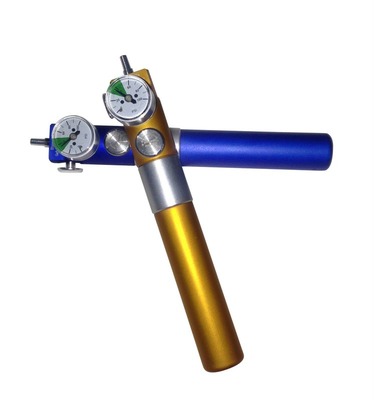

Karboksyterapia, do niedawna zabieg dostępny tylko dla lekarzy medycyny estetycznej, teraz dzięki aparatowi N-CDT Skin Breath dostępny także dla gabinetów kosmetologii estetycznej. Wymierne efekty sprawiają, że zabiegi te cieszą się niesłabnącym powodzeniem. Karboksyterapia jest uznawana za jeden z najbardziej holistycznych zabiegów, jest to procedura bardzo mało inwazyjna, a o spektakularnych efektach.

Dwutlenek węgla został uznany za „cudowny gaz” przez światowej sławy lekarzy medycyny estetycznej. Gaz ten stosujemy z powodzeniem w dużej ilości wskazań. Nie trzeba już inwestować w wiele różnych urządzeń by sprostać różnorodnym oczekiwaniom klientów gabinetu.

Aparat N-CDT Skin Breath rozszerzy ofertę o kluczowe zabiegi:

-

redukcja cieni pod oczami do 90%

-

zmarszczki wokół oczu do 60%

-

blizny trądzikowe do 90%

-

usuwanie zmarszczek do 60%

-

redukcja cellulitu do 90%

-

to tylko niektóre z możliwości zabiegu.

Odrobina historii

Krajem w, którym po raz pierwszy wykorzystano CO2, była Francja. Zabiegi z użyciem tego gazu stosowano w leczeniu choroby tętnic obwodowych. Kardiolodzy zalecali pacjentom kąpiele w wodzie nasyconej CO2. Metodę tę stosuje się do dziś w uzdrowiskach i sanatoriach. Jej trwałe efekty, skłoniły lekarzy do stworzenia procedur wstrzykiwania CO2 śródskórnie i podskórnie. Dziś, dzięki aparatowi N-CDT Skin Breath podajemy gaz w sposób bardzo precyzyjny i pod kontrolowanym ciśnieniem.

Co czyni ten gaz – CO2, tak wyjątkowym?

Dwutlenek węgla jest naturalnym produktem metabolizmu komórkowego w naszym organizmie. Przedawkowanie tego gazu jest niemożliwe, nadmiar CO2 jest natychmiast wydalany z organizmu, co czyni karboksyterapię wyjątkowo bezpieczną.

Cała chemia

W momencie podania CO2 mózg odbiera sygnał o niedotlenieniu organizmu. Rozszerzają się naczynia krwionośne i wzrasta przepływ krwi, co prowadzi do lepszego odżywienia i dotlenienia tkanek. W znacznym stopniu zwiększają się procesy rewaskularyzacji i neowaskularyzacji.

Dwutlenek węgla po podaniu do tkanek wchodzi w reakcję z wodą tworząc kwas węglowy. Pod wpływem enzymu anhydrazy węglanowej, kwas ten rozkłada się na kationy wodoru i jony wodowęglanowe, co prowadzi do zmiany pH otoczenia – na kwaśne. Ma to bardzo duże znaczenie, ponieważ hemoglobina pozbywa się z cząstek tlenu w środowisku kwaśnym, dużo szybciej. W rezultacie obszar zabiegowy zostaje mocno dotleniony.

Zmiana pH na kwaśne wraz z drugim zjawiskiem: rozerwania połączeń między poziomymi warstwami skóry, prowadzi do wytworzenia stanu zapalnego. W rezultacie zwiększa się w organizmie stymulacja produkcji włókien kolagenu i elastyny, oraz poprawia się gospodarka wodna organizmu. Czego efektem jest wzmocnienie napięcia skóry i zwiększenie jej grubości.

Zabieg

Zabieg

Dyskomfort pacjenta jest minimalny. Wiąże się on z nakłuciem i lekkim szczypaniem podczas podawania gazu. Towarzyszy temu zaczerwienienie okolicy zabiegowej, które zniknie po zabiegu w krótkim okresie czasu, samoczynnie.

N-CDT Skin Breath podaje gaz 90 ml/min pod kontrolowanym ciśnieniem 2-3 barów.

Dwutlenek węgla jest ok. 20 krotnie łatwiej rozpuszczalny od tlenu, wchłania się bardzo szybko, a po ok. 5 min jego nadmiar jest wydalany z organizmu wraz z wydychanym powietrzem. Nie istnieje ryzyko powikłań.

Nasz Cel

W niniejszym artykule chcieliśmy przybliżyć Państwu główne zalety Karboksyterapii. Jesteśmy bezpośrednim importerem i dystrybutorem Aparatu do Karboksyterapii N-CDT Skin Breath. Zapewniamy korzystną cenę, serwis gwarancyjny i pogwarancyjny oraz (co jest wyjątkowe na rynku) stałe doradztwo wykwalifikowanych szkoleniowców. Nasi Klienci mogą liczyć na profesjonalne materiały marketingowe.

Źródło: http://n-symbiosis.com/